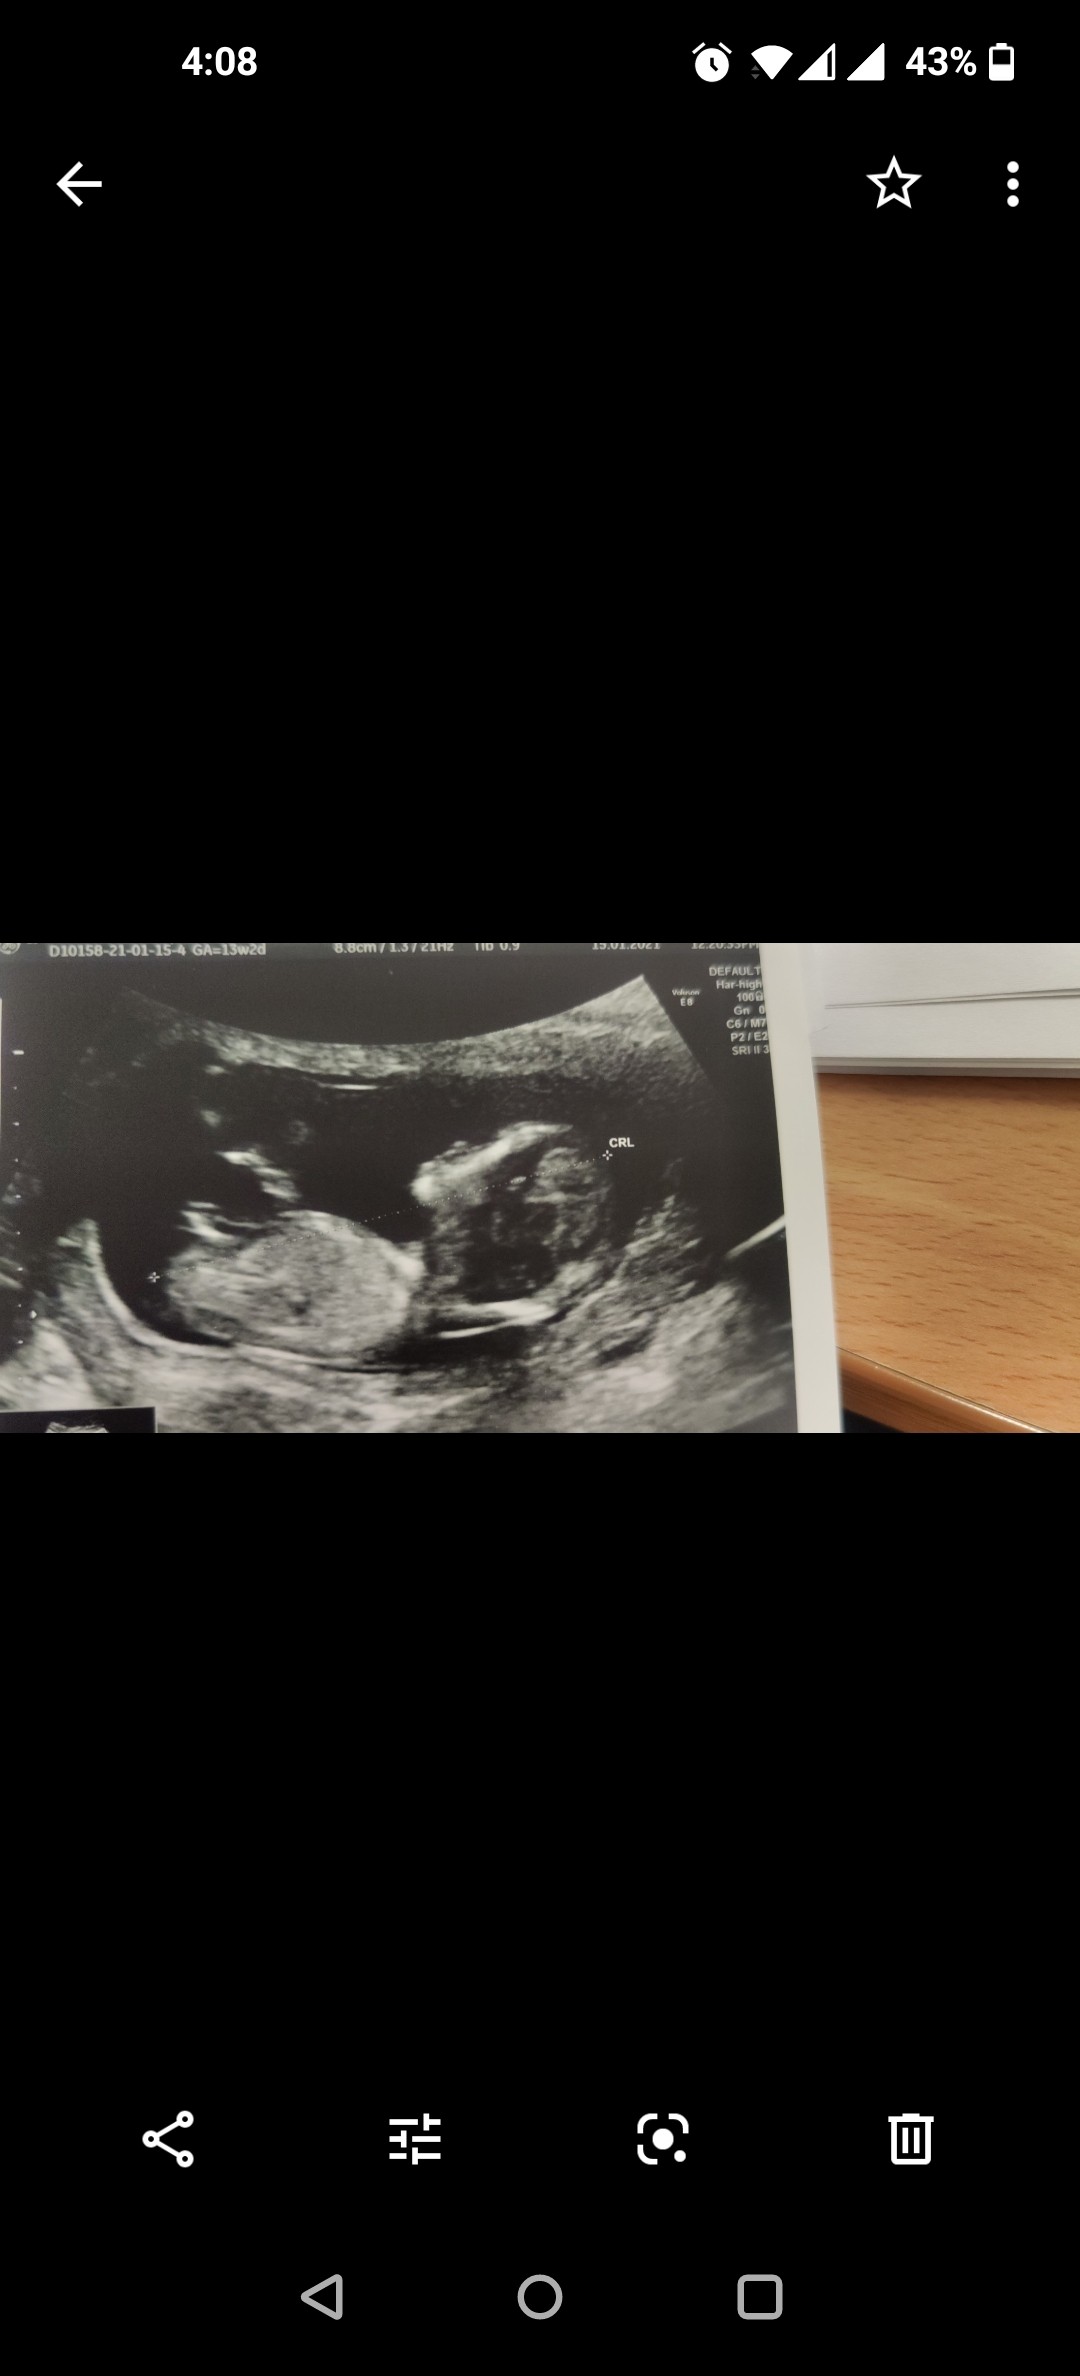

Usg chłopak czy dziewczynka

Witam w 19 tygodniu ciąży dowiedziałam się ze będę miała dziewczynkę w 20 tyg okazało się jednak , że to chłopak. Sama już nie wiem bo na jednym usg widać na pewno dziewuche a na drugim chłopca. Może to pempowina ?? Może ktoś mi pomoże rozwiązać ta zagadkę

Załączniki

• 4A8F5FF1-76CA-4DE0-AC12-5EDF08E820F2.jpg

4A8F5FF1-76CA-4DE0-AC12-5EDF08E820F2.jpg

596,4 KB · Wyświetleń: 44 138